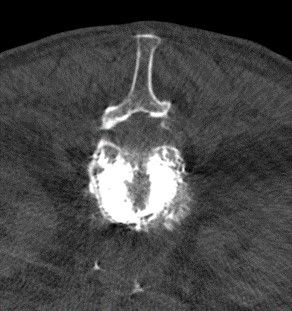

Nové robotické rameno přináší výrazně lepší kvalitu zobrazení. Díky rychlému mobilnímu rotačnímu mechanizmu, umožňujícímu libovolný pohyb v 3D prostoru, zaručuje zvýšení bezpečnosti těchto výkonu především u pacientů s těžkou osteoporózou nebo významnou obezitou, kde klasický rentgen má svá technologická kvalitativní omezení. Dalším významným benefitem během takové operace je možnost CT vyšetření při kontrole plnění obratlů cementem. Přístroj zobrazí přesné šíření cementu a vyloučí jeho únik mimo obratle.

CT kontrola šíření cementu po kyfoplastice. Foto: Krajská zdravotní